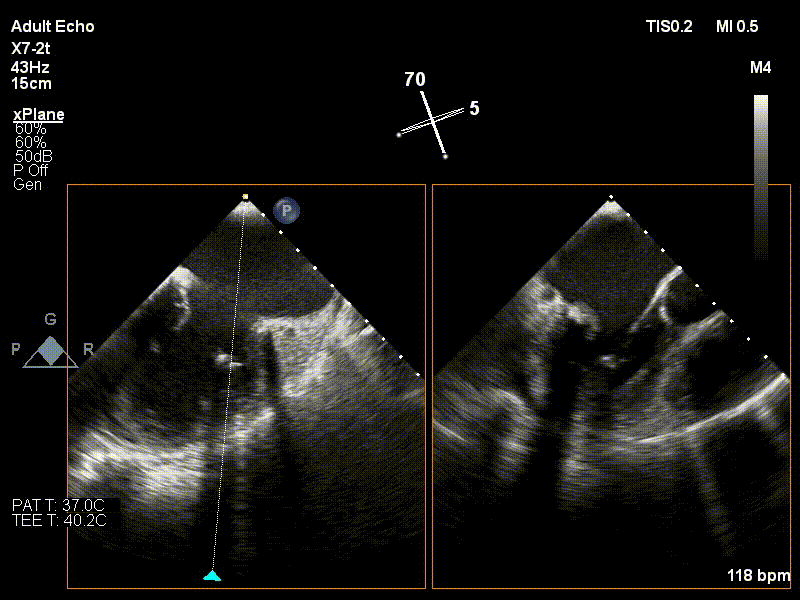

术前行经食道超声评估

原发性二尖瓣反流,前后叶广泛脱垂,Barlow病变,反流程度4+;二尖瓣瓣口面积3.85cm²,平均跨瓣压差3mmHg;LA42mm,右房大小55×66mm;二尖瓣前叶(A2)长度29mm,二尖瓣后叶长度(P2)长度21mm;左室射血分数60%,肺动脉压增高43mmHg。